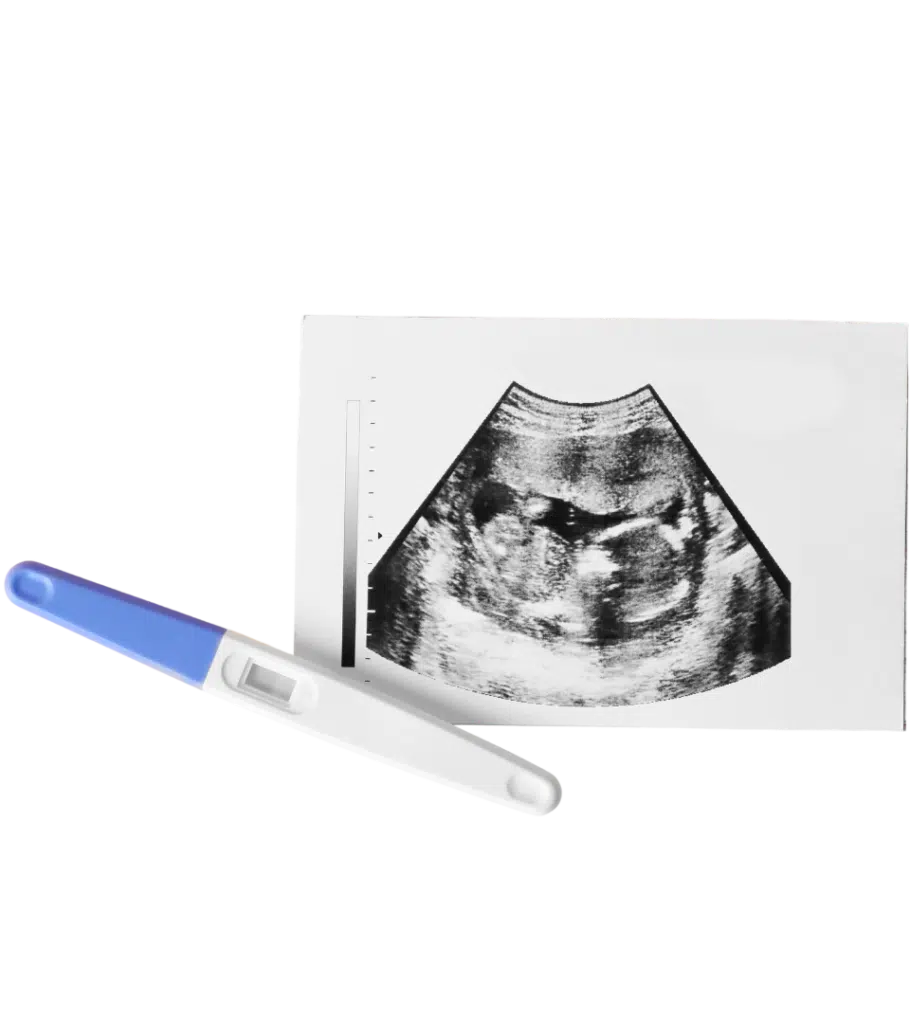

Ultrasound

Ultrasound tells you what is happening now.

When you have a positive pregnancy test and have been offered STI/STD testing, the next step is confirming the pregnancy with an ultrasound. An ultrasound provides real-time information when making a pregnancy decision. Having a pregnancy confirmed by ultrasound can also help you get medical care started.

An ultrasound provides an image of what is happening inside your body. This image provides information to you that is unavailable otherwise. Our sonographer (a trained technician in obstetrical scanning) will apply gel to your abdomen. She will then use a hand-held device called a transducer against the area being studied. The transducer sends soundwaves into your body to capture the images.

A positive pregnancy test can tell what happened in the recent past.  You got pregnant.  However, because up to 20% of known pregnancies and as many as 40% of total pregnancies end on their own, you may still have hCG in your urine but no longer have a live pregnancy.  An ultrasound is the only way to confirm if your pregnancy is still viable (developing), a critical piece of information if you are making a pregnancy decision.

An ultrasound will answer three important questions:

• Is your pregnancy viable? Is there a detectable fetal heartbeat that indicates that the pregnancy is developing.

• How far along are you? Ultrasound in the first trimester can closely determine how many days or weeks pregnant you are by dating the pregnancy.

• Is your pregnancy located in your uterus? Sometimes, a pregnancy can begin to grow in the wrong area, typically the fallopian tube. This is called an ectopic pregnancy and is life-threatening.

Determining viability is important because up to 20% of pregnancies end on their own in miscarriage.  Only an ultrasound can determine if you have miscarried TODAY.  Additionally, if you are considering abortion, it is crucial that you know how far along you are. This will determine the type of procedure available to you and how much it would cost.